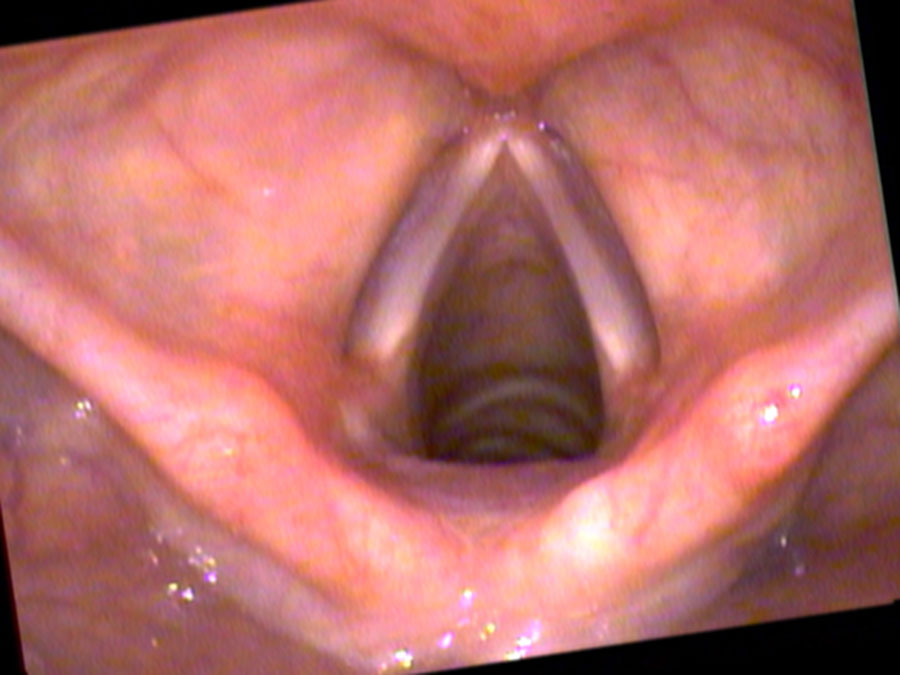

2012-11-06_vid1-003102-ab Previous Next Published October 11, 2017 at 900 × 675 in Singing in the Rain – An Update